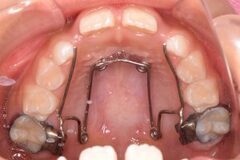

床矯正装置 取り外し可能なプレート状の装置で、ネジを回して顎を広げます。主に顎の成長不足が原因の歯並びを改善します。